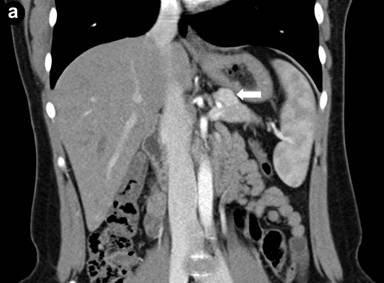

An abdominal contrast-enhanced computed tomography scan showed a 10x12x17 mm, small, well-demarcated, heterogeneously enhancing lesion within the body of pancreas without dilatation of pancreatic duct. No evidence of lymphadenopathy or distant metastasis was identified (Figure 1). Subsequently, patient was scheduled for laparotomy.

Figure 1. Coronal (a.) and transverse (b.) views of abdominal contrast-enhanced computed tomography scans: showing a 10x12x17 mm, small, well-demarcated, heterogeneously enhancing lesion within the body of pancreas (white arrow) without dilatation of pancreatic duct. No evidence of lymphadenopathy or distant metastasis was identified. |